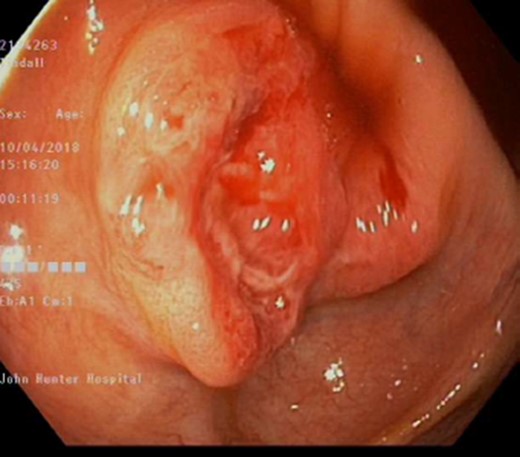

Apart from an occasional flare of his inflammatory bowel disease, requiring corticosteroids, he has been well. During his most recent screening colonoscopy he was found to have a 25 mm polypoid, sessile, friable, ulcerated lesion in his caecum (Fig. 1). The patient underwent a mucosal biopsy for further histological analysis. There was no other abnormality detected. This is in the context of no cardinal symptoms, and otherwise being completely asymptomatic.